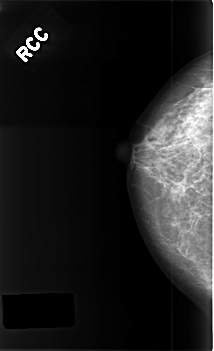

C_0385_1.RIGHT_CC

RIGHT_CC LINES 4560 PIXELS_PER_LINE 2776 BITS_PER_PIXEL 12 RESOLUTION 50 NON_OVERLAY